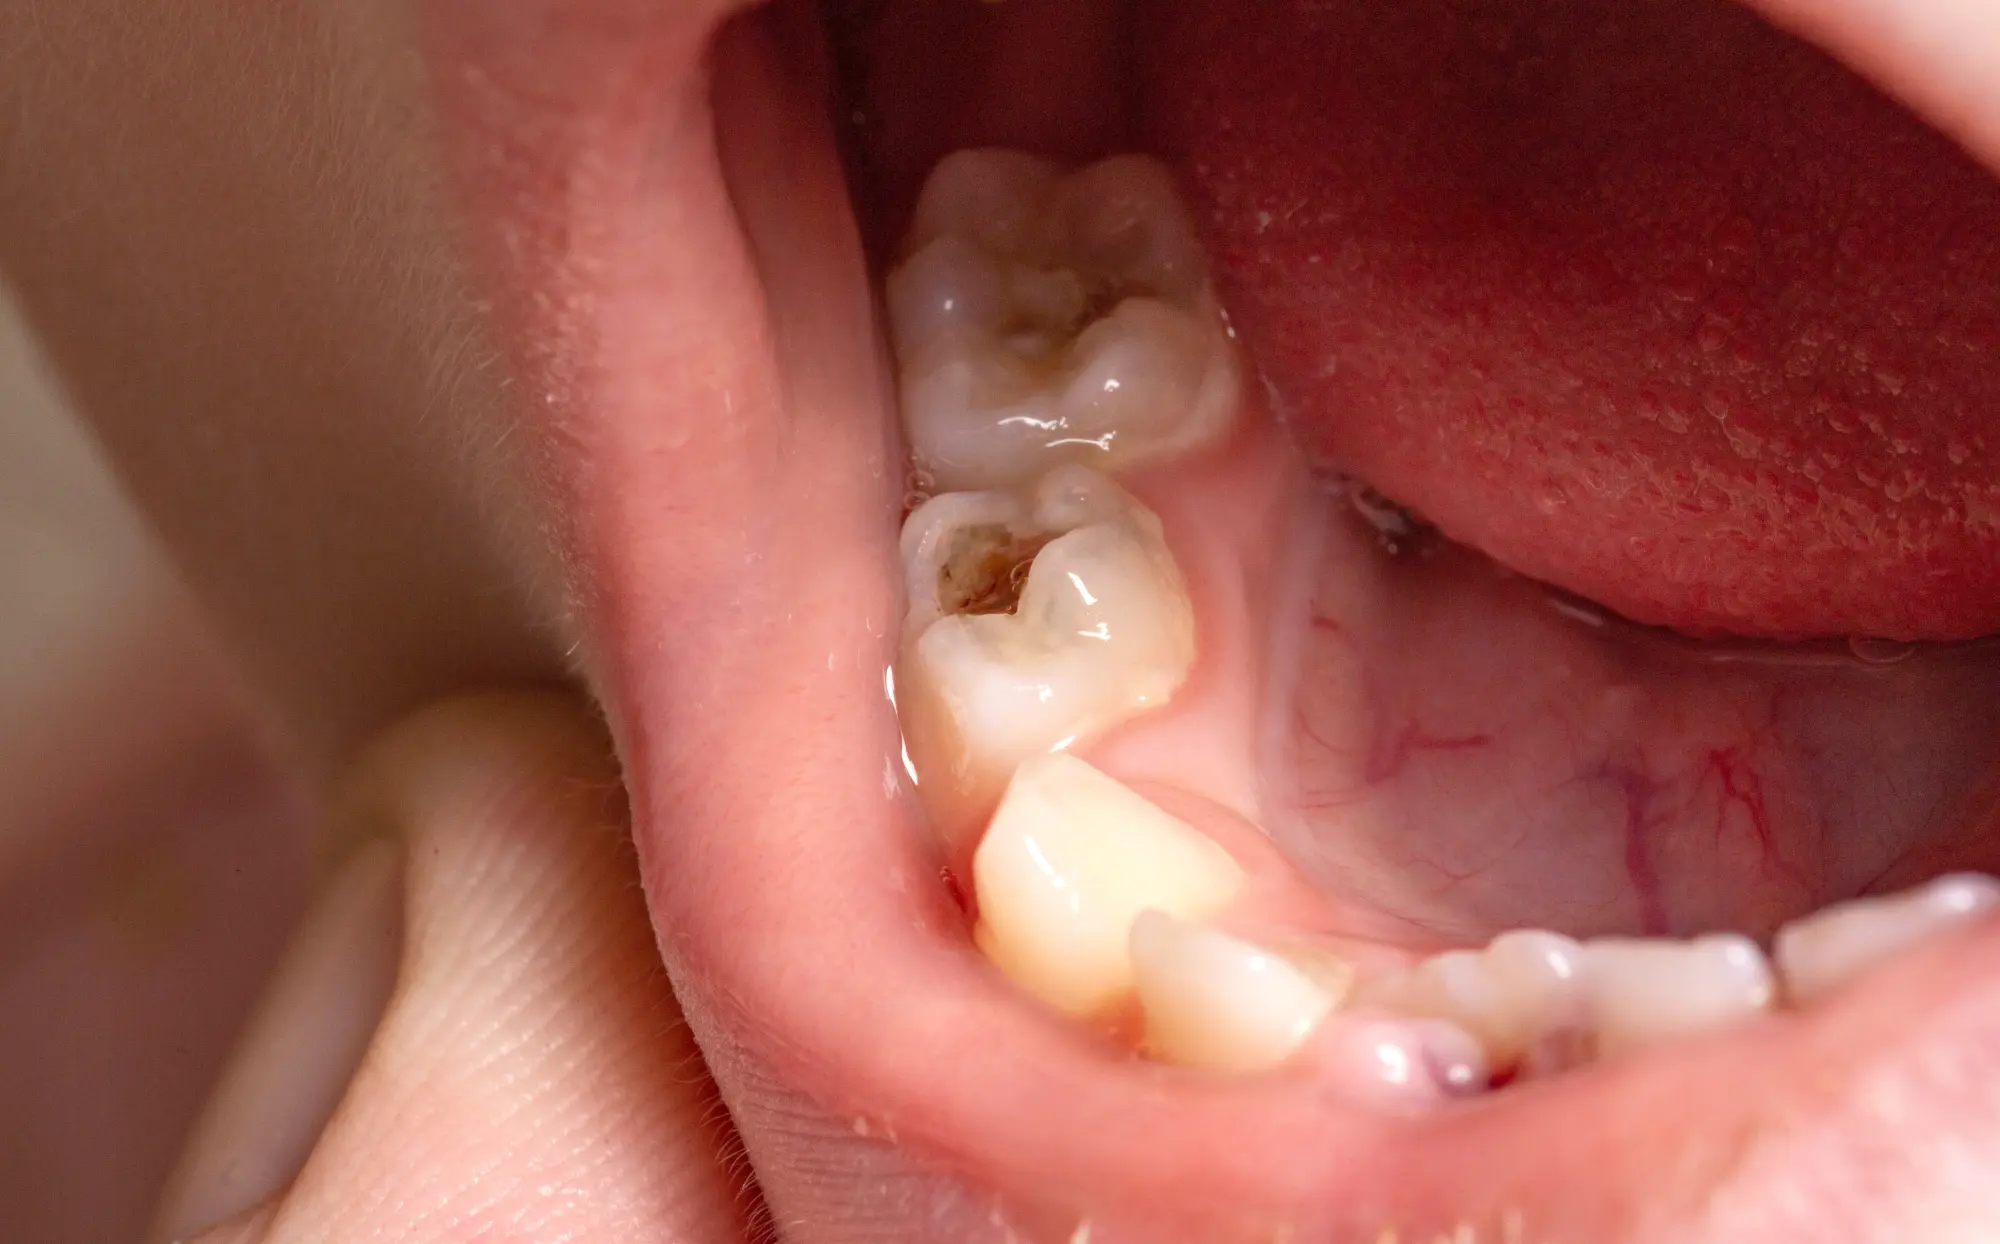

Cavities, also known as dental caries or tooth decay, are holes that develop in the teeth due to decay. They are caused by a combination of factors, including poor oral hygiene, frequent snacking, and consuming sugary drinks. Here are some key points to understand about cavities:

When a cavity is detected, various treatment options are available depending on the severity. Here’s what you might expect: